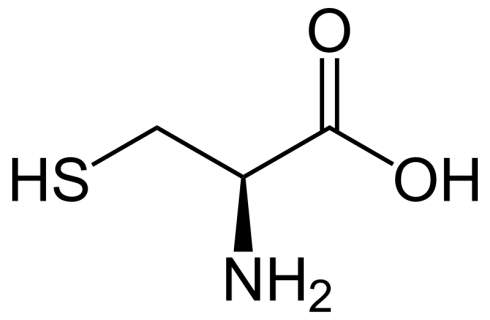

سیستئین چیست؟ آشنایی با اسید آمینه سیستئین

سیستئین نوعی اسید آمینه است که با فرمول شیمیایی HO2CCH(NH2)CH2SH یافت میشود و در بدن[بیشتر بخوانید]

2 دیدگاه